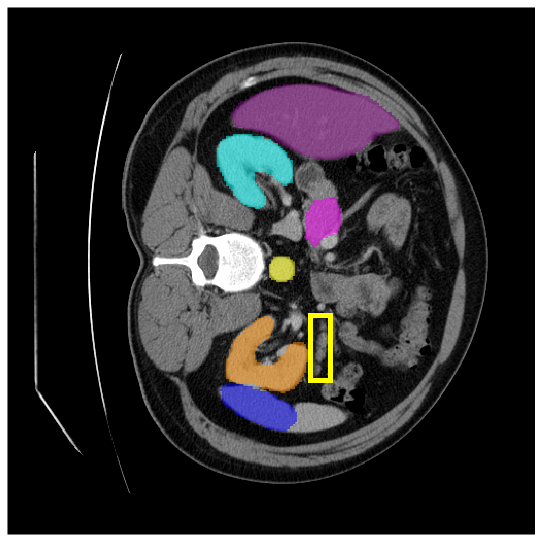

Our model is evaluated on the Synapse [25] and ACDC [24] datasets. Synapse is an abdominal CT image dataset with 30 images containing eight organs: the aorta, gallbladder (GB), left kidney (KL), right kidney (KR), liver, pancreas (PC), spleen (SP), and stomach (SM). 18 and 12 scans are used for training and evaluation, respectively. ACDC provides MRI data containing three organs of 100 patients: the right ventricle (RV), left ventricle (LV), and myocardium (Myo). 70 images for training, 10 for validation, and 20 images for evaluation are used.

4.3.2 Visual Comparisons

Visualization of our method on the Synapse and ACDC datasets is shown in Fig. 3(a) and Fig. 3(b). For the Synapse dataset illustrated in Fig. 3(a), FCT failed to accurately segment SM and GB, while MERIT achieved precise segmentation of SM but struggled with GB. In contrast, our method achieved accurate segmentation of both SM and GB. Regarding the ACDC dataset shown in Fig. 3(b), while previous methods achieve comparable segmentation of the Myo and LV to the GT, they exhibit noticeable errors on the RV, including invasion into adjacent organs and misrecognition. On the other hand, our method accurately segments across all three structures Myo, LV, and RV, performing as precisely as the GT. We demonstrate the superiority of our method quantitatively and qualitatively.